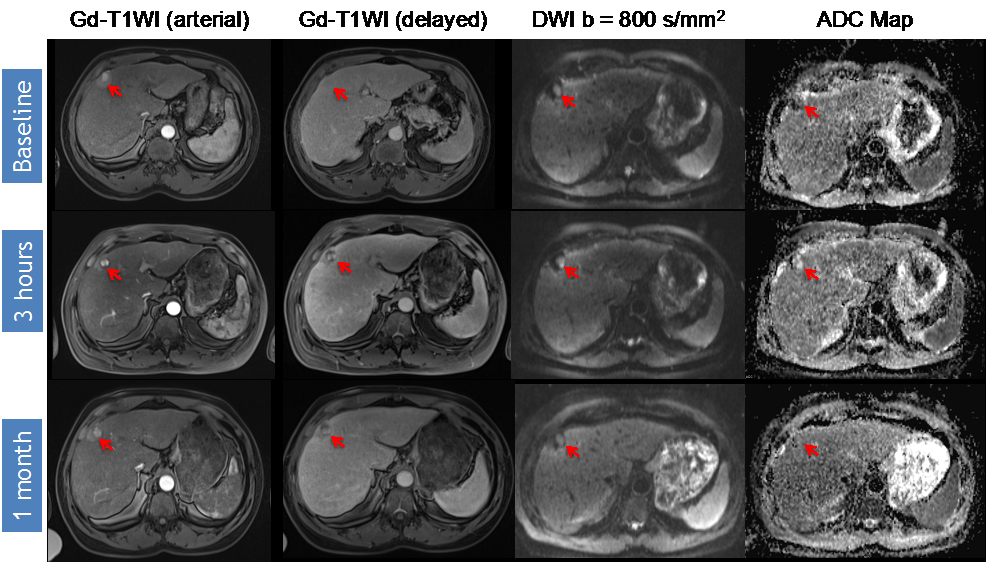

DWI Response Assessment after DEB-TACE treatment. 55-year-old woman presented with a segment VII HCC (arrow) previously treated with DEB-TACE without macrovascular invasion or extrahepatic disease. Note that there is initial absence of enhancement at 3 h, but the area continues to demonstrate restricted diffusion (ADC 0.904 × 10−3 mm2/s). At one month, the same area now demonstrates enhancement with increased restricted diffusion, findings consistent with progression of disease (PD) (baseline ADC 0.904 × 10−3 mm2/s, post-3 h ADC 1.02 × 10−3 mm2/s, post-one month ADC 0.830 × 10−3 mm2/s).

Identifying early disease progression or absence of response to locoregional therapies is imperative and allows for individualized therapeutic strategies and potentially improved overall prognosis in patients. Volumetric ADC changes after conventional TACE (cTACE) have been investigated at one month after therapy and correlated with six-month RECIST and mRECIST objective responses [27]. Increases in volumetric ADC values to 1.6 × 10−3 mm2/s in at least >39.8% of the tumor volume correlates with objective response by mRECIST at six months with a sensitivity of 88.4% and specificity of 78.6% (p = 0.001). Similar results were obtained by using RECIST response criteria, albeit with lower sensitivity and specificity [27]. An absolute increase in ADC values has also been observed in responding lesions compared to non-responders by mRECIST criteria for cTACE [28]. Kokabi et al. [29] demonstrated a % ADC increase for responders vs. non-responders (36.4% vs. 7.4%; p < 0.001) 3 h after DEB-TACE intervention, which further increased after one and three months (98.1% and 115.2%) for responders, whereas no relevant increase for non-responders (−0.1% and 2.1%, p > 0.05) was evident. Exemplary diffusion-weighted imaging cases from this study with complete response (Figure 1), partial response (Figure 2), and progressive disease (Figure 3) are illustrated below. A significant percent increase in ADC values has also been reported by another study in responding lesions one and three months post-DEB-TACE compared to non-responders by mRECIST and EASL criteria [30].

Variable timelines in terms of changes in DWI were reported with some studies demonstrating significant changes in treated lesions within 24 h [29,43,46], 2–3 days [10] or 5–7 days [45] after therapy, all of which could predict the outcome. However, another study only detected a significant ADC change following 1–2 weeks after treatment but not before or after that time period [47]. Kokabi et al. [29] demonstrated a continuous increase of obtained ADC values during the course of three months for objective treatment responders but not for non-responders after DEB-TACE (Figure 1, Figure 2 and Figure 3). Chung et al. [46] investigated intraprocedural DWI changes following cTACE and did not detect a significant % ADC change (3%; SD: ±16.4%) in treated lesions. However, an intraprocedural relative ADC value increase or decrease of ≥15% of individual lesions was associated with a 100% positive predictive value, a specificity of 100%, and a sensitivity of 46% for tumor response after 1 month (EASL) following cTACE.